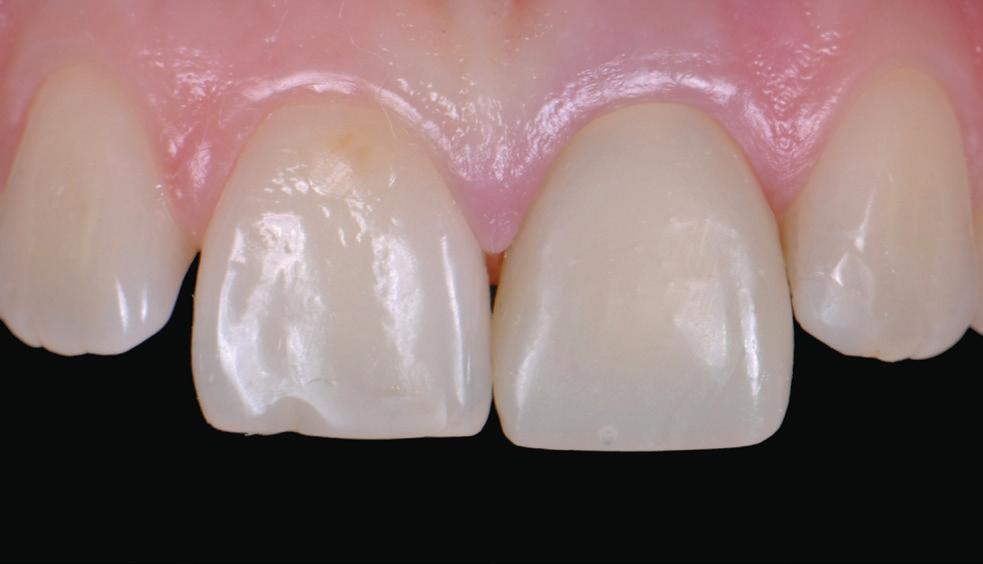

Knowing your own practice.

Often sales processes reveal that dentists have not understood their strengths and weaknesses and expose themselves to shocks during the selling process. Most accountants simply churn out tax returns for a variety of small businesses and individuals with no idea regarding how a dental practice compares with key benchmarks. These accountants are inadequate in representing their dental clients if a sale process reveals weakness whereas their client had assumed that they would have been advised by their accountant of issues that they should have addressed long before listing for sale.

Practice managers negative impact on profit and sale price.

Unfortunately, most practice managers —other than courtesy titles given to experienced receptionists—are profit destroyers rather than profit enhancers.

“Innocent” asked for a practice valuation and was shocked at the low figure. He sought deeper analysis and I pointed out that his non-clinical staff cost as a percentage of practice fees was extraordinarily high. With superannuation and work cover insurance, the “manager” was costing his practice $110,000 per year—and this was quite a few years back. The remainder of the non-clinical staff together cost as much as the average of all dental practices. The manager was not saving on other staff and her cost effectively reduced the capital value of his practice by around $400,000. He took a deep look at what the manager actually did and found out that with the assistance of a visiting bookkeeper and a bit of tightening of dental patient appointments and chairside assistants’ hours, he could dispense with the manager, reducing non-clinical staff overhead by $110,000. The practice manager’s position had long been redundant. A couple of years later he was able to sell his significantly more profitable practice for its true value.

Preparing to buy a dental practice.

The first thing to understand is that the vast majority of accountants and financial advisers know “diddly squat” about the differences between good and mediocre dental practices.

If they do have one or two dental clients, their interaction is invariably limited to completing annual tax and financial returns, but they are clueless as to how their clients’ practices compare with wellperformed practices or what to advise a buyer to look for beyond averaging the last three years’ profits.

Accountants’ advice seriously lacking

While many accountants have signage proclaiming that they give “business advice”, most do tax returns and confine advice to tax issues.

There is no point in comparing a dental client with a plumbing contractor or an Australia Post and lottery agent. Wisdom does not appear to improve with size of accounting practices. I have seen accountants from top-end-of-town accounting groups badly let down dentists with misinformed advice.